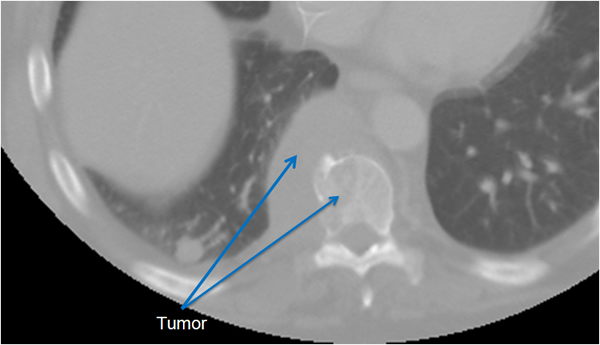

The thoracic spine can be approached through the right or left chest and communication with the spine surgeon is mandatory so that the approach and extent of exposure can be tailored appropriately. In the absence of lateralizing pathology, either a right or left-sided thoracotomy can be used to expose the thoracic spine. As a general rule, the upper thoracic spine (T2-9) is better approached from the right side because of the location of the heart, aortic arch and great vessels. Conversely, in the case of the thoracolumbar spine (T10-L2) a left-sided thoracotomy is preferred to avoid liver retraction. The side of approach must provide maximum exposure to the pathology to be treated. Local factors such as previous thoracotomy, pleurodesis, or infection should also be considered. In general, a right sided approach provides more direct access to the spine, as the mediastinal structures lie to the left of the vertebral bodies. CT and MRI allow for a precise evaluation of the anatomy of the spine pathology and the related intra-thoracic structures (Figures 1a, 1b).